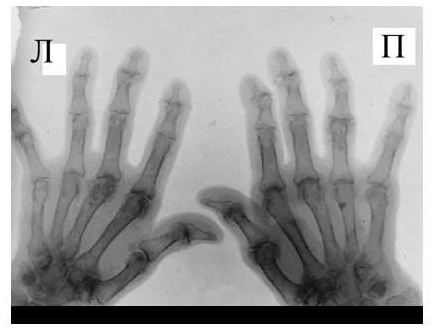

Рис. 3 Сочетание ревматоидного артрита и остеоартроза

Большинство ошибок встречаются при начальных стадиях, особенно при начале РА в пожилом возрасте и сочетании его с остеоартрозом (см. рис. 3). В этом случае для подтверждения диагноза РА и предупреждению случаев его гипердиагностики служит выявление симметричных эрозий в типичных для ревматоидного артрита суставах (запястья, плюснефаланговые, пястно-фаланговые).

Рис. 4. Изменения кистей при ревматоидном артрите (а остеопороз, бсужение суставных щелей, в кистовидные просветвления, г костные эрозии, д анкилозирование)

Необходимо также помнить, что, как правило, при РА эрозии не предшествуют околосуставному остеопорозу, кистам и сужению суставных щелей. Имеет место последовательность развития стадий РА (см. рис. 4), в отличие от эрозивных артритов другого генеза (псориатического, серонегативного)